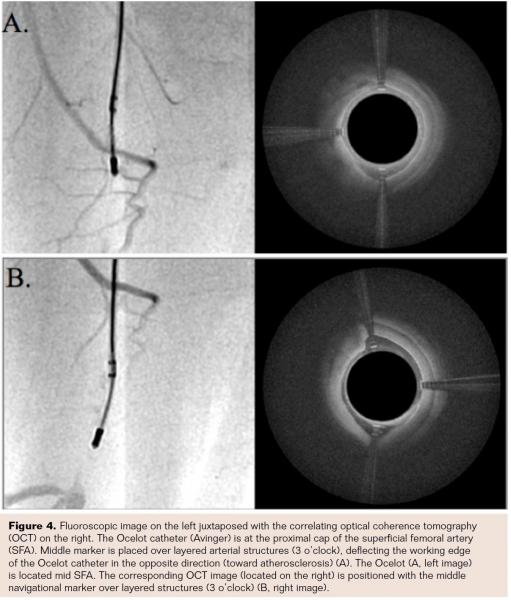

Sixteen CTOs in 15 patients (100%) were crossed successfully using a standalone Ocelot catheter. The OCT-guided intraluminal crossing was performed within the luminal to medial boundaries of the artery (within the true lumen), without the need for subintimal tracking and without requiring ancillary crossing wires or other support catheters. The crossing precision of the studied OCT lesions was enabled due to the targeted mode of Ocelot catheter progression: the Ocelot catheter is advanced through the fibrotic or stenotic CTO occlusions based on the rotation of spiral wedges located on the tip of the catheter, in both clockwise and counterclockwise directions (Figure 2). The OCT radiopaque directional markers (Figures 2 and 3) allow for the placement of the distal tip within the occlusive CTO tissue, opposite and away from the healthy vascular lumen boundary (layered tissue, Figure 4). In this cohort, no dissections or perforations were noted. The therapeutic recanalization of the crossed lesions was then completed using a combination of therapies, including angioplasty and/or atherectomy, as preferred by the operator and based on the clinical indication. Notably, because of the intraluminal recanalization, no stent placement was required.